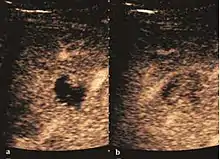

The ultrasound appearance is a well defined lesion, with very thin, almost unapparent walls, without circulatory signal at Doppler or CEUS investigation. The content is transonic suggesting fluid composition. The presence of membranes, abundant sediment or cysts inside is suggestive for parasitic, hydatid nature. Posterior from the lesion the acoustic enhancement phenomenon is seen, which strengthens the suspicion of fluid mass. They typically displace normal liver vessels but no vascular or biliary invasion occurs.

Liver cyst

Hydatid liver cyst. Diagnostic criteria are the presence of membranes and sediment inside.